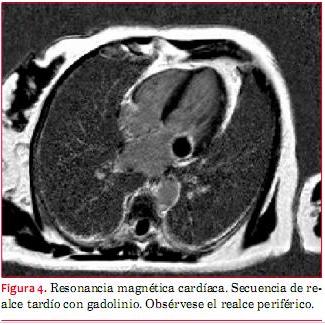

La resonancia nuclear magnética cardíaca objetivó a nivel del anillo mitral, sector posterolateral, una masa vinculada al mismo, de bordes bien definidos y en contacto con el segmento basal del velo posterior. En las secuencias de cine (eco de gradiente - SSFP), la misma se vio hipointensa con respecto al miocardio adyacente, al igual que en las secuencias de sangre negra (T1) y de edema (T2). No se observó defecto de perfusión en las secuencias de perfusión de primer paso (figura 3).

En las secuencias de realce tardío se observó la presencia de realce periférico sin captación del contraste en el centro de la masa (figura 4).

La resonancia se considera la técnica de elección en los casos dudosos. Los hallazgos típicos en las distintas secuencias incluyen: señal hipointensa con respecto al miocardio en secuencias de eco gradiente y en las secuencias T1 y T2, ausencia de perfusión y de captación precoz de contraste. La mayoría tampoco presenta realce tardío, aunque puede observarse en algunos casos realce periférico en relación con una cápsula fibrosa(3,6).